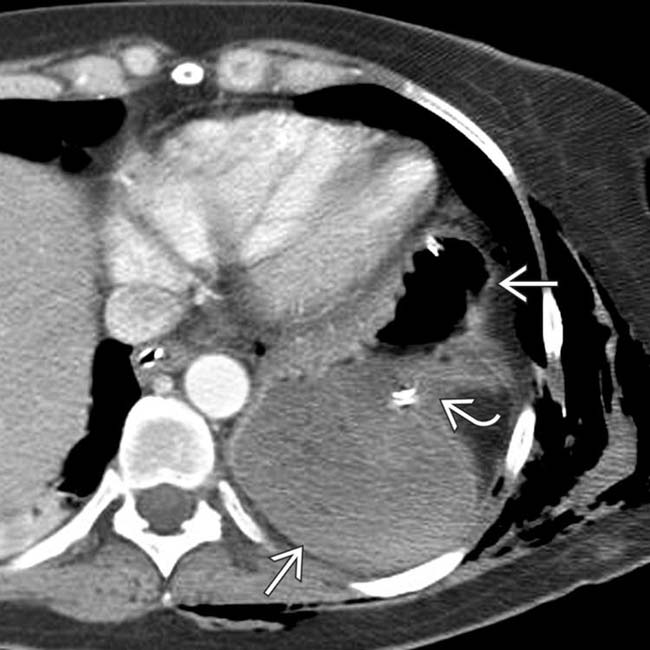

Imaging of Diaphragmatic Injury A Diagnostic Challenge? RadioGraphics

Traumatic Diaphragmatic Rupture Radiology Key Can The Diaphragm Be Damaged Traumatic injury to the diaphragm is rare. Phrenic nerve damage can cause your diaphragm to stop working properly, making it hard to breathe and live normally. Learn about the possible causes of diaphragm pain, such as muscle strain, acid reflux, or hiatal hernia, and how to alleviate it with rest,. It can occur, however, with penetrating trauma (stab wounds) or. Can The Diaphragm Be Damaged.

Traumatic Diaphragmatic Rupture Radiology Key Can The Diaphragm Be Damaged Traumatic injury to the diaphragm is rare. A tight diaphragm can cause pain in the side, chest, neck, and shoulders, as well as shortness of breath, hiccups, and indigestion. It can occur, however, with penetrating trauma (stab wounds) or blunt force trauma. Phrenic nerve damage can cause your diaphragm to stop working properly, making it hard to breathe and live. Can The Diaphragm Be Damaged.

From pubs.rsna.org

Imaging of Diaphragmatic Injury A Diagnostic Challenge? RadioGraphics Can The Diaphragm Be Damaged Phrenic nerve damage can cause your diaphragm to stop working properly, making it hard to breathe and live normally. Learn about the causes, symptoms and treatments of diaphragm paralysis, a condition that affects breathing and is often caused by. Learn about the causes, symptoms,. A tight diaphragm can cause pain in the side, chest, neck, and shoulders, as well as. Can The Diaphragm Be Damaged.